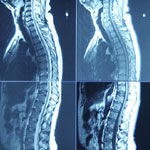

ניתוח פריצת דיסק: נא לא לאחר

מחקר ישראלי על ניתוחים בפריצות דיסק קובע: איחור בביצ...

פריצת דיסק: טיפול ללא ניתוח

ניתן לטפל בפריצת דיסק ובבלט הדיסק ללא ניתוח או תרופו...

עקמת - אבחון, מעקב וטיפול

לא תמיד ניתן למנוע עקמת, פיתולים חריגים בעמוד השדרה....

כאבי גב - כיצד מטפלים בפריצת דיסקוס?

מבין התסמונות של כאבי גב, 'פריצת דיסקוס' היא השכיחה...